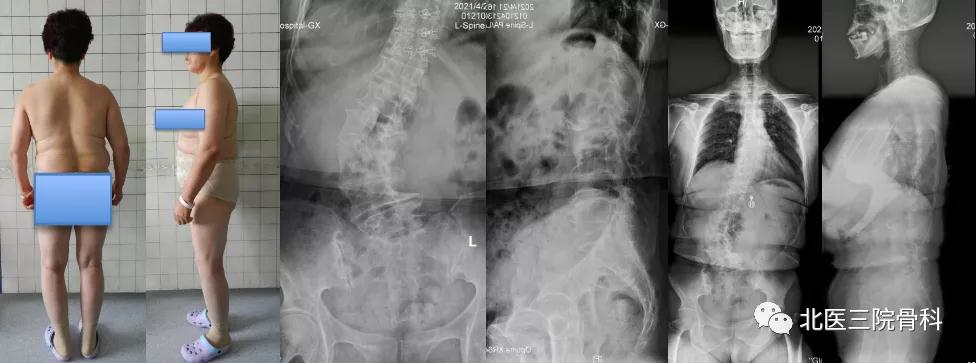

陈旧结核性胸腰椎后凸畸形

大体照及影像学(术前)

大体照及影像学(术后)

自本世纪初开始,陈仲强教授针对胸腰椎畸形展开积极探索,先后应用经关节突椎间隙联合椎弓根闭合截骨、前方垫高-后方闭合截骨矫形和节段切除-双轴旋转矫形等手术方法,分别针对陈旧创伤性胸腰椎后凸、先天性脊柱后凸和陈旧结核性脊柱后凸等疑难病症进行矫形手术治疗并取得良好疗效,特别是在脊柱陈旧结核性角状后凸领域取得了重大进展,其治疗难度和效果达到国际领先水平,获得北京市科技技术奖和北京市科委首都十大疾病重大科技进展创新奖。